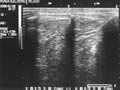

<参考> ACL断裂のエコーでの確認

当院では、症状の適切な評価のために、エコー(超音波画像)による観察も行っております。